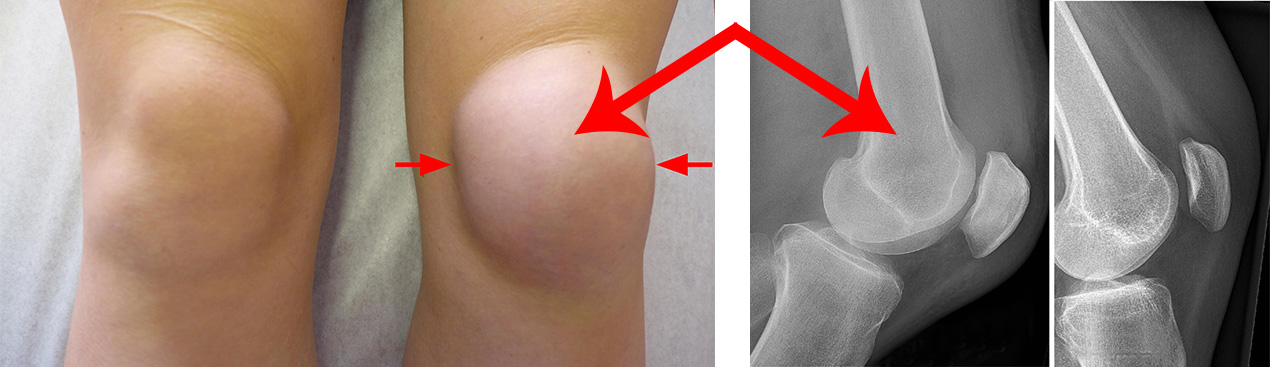

Если после удара коленом образовалась жидкость с целью исключения перелома рекомендую выполнить рентгеновские снимки или пройти МРТ исследование.